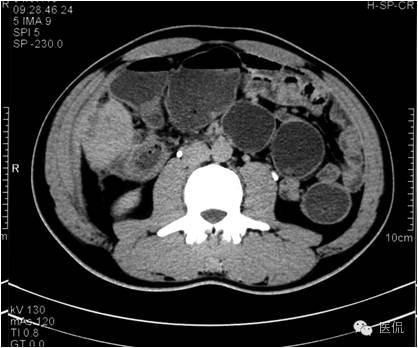

动脉期病灶显示小片状低密度影内,见不规则环状、核心样点状和间隔轻度强化,形态多种。